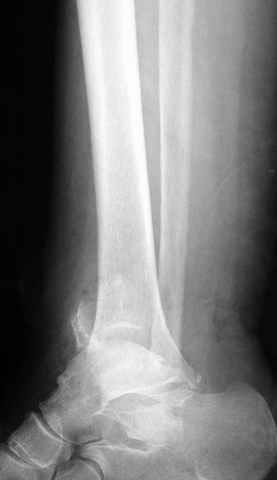

Dear all,40 y.o. man had sustained this terrible fracture falling from a motorbike.

Closed fracture.

This is really Pilon Fx (C3.3; the high energy and the extent of distal tibia comminution are defining it).